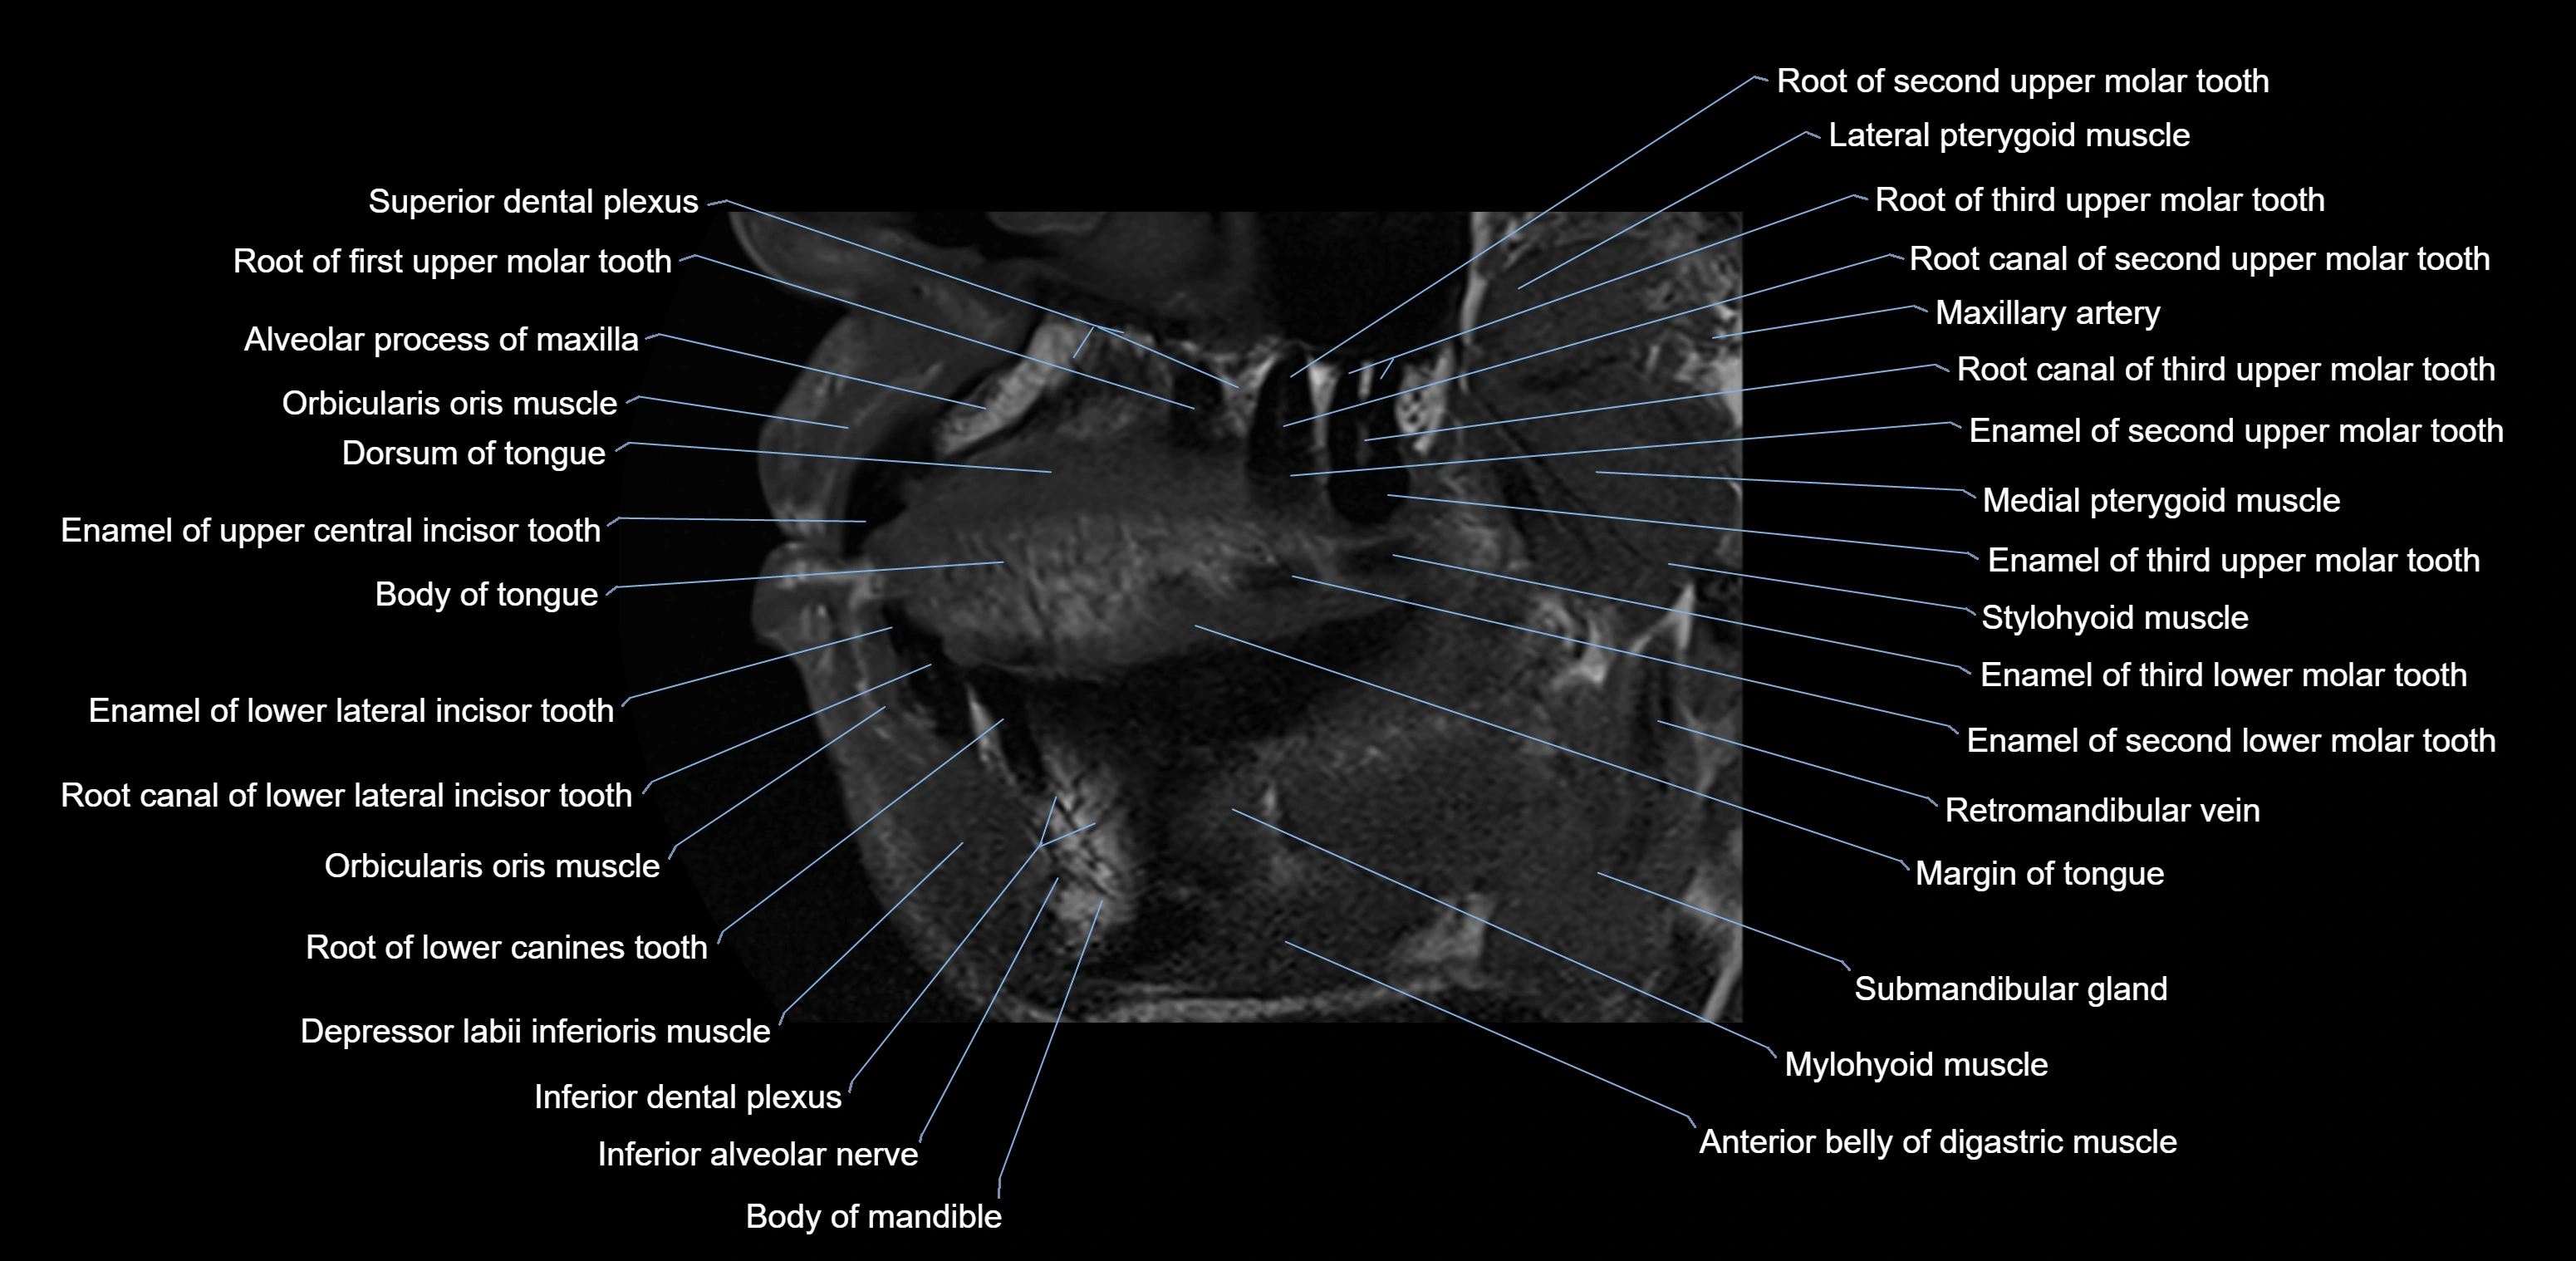

- Body of tongue

- Dorsum of tongue

- Inferior alveolar nerve

- Mylohyoid muscle

- Stylohyoid muscle

- Superior dental plexus